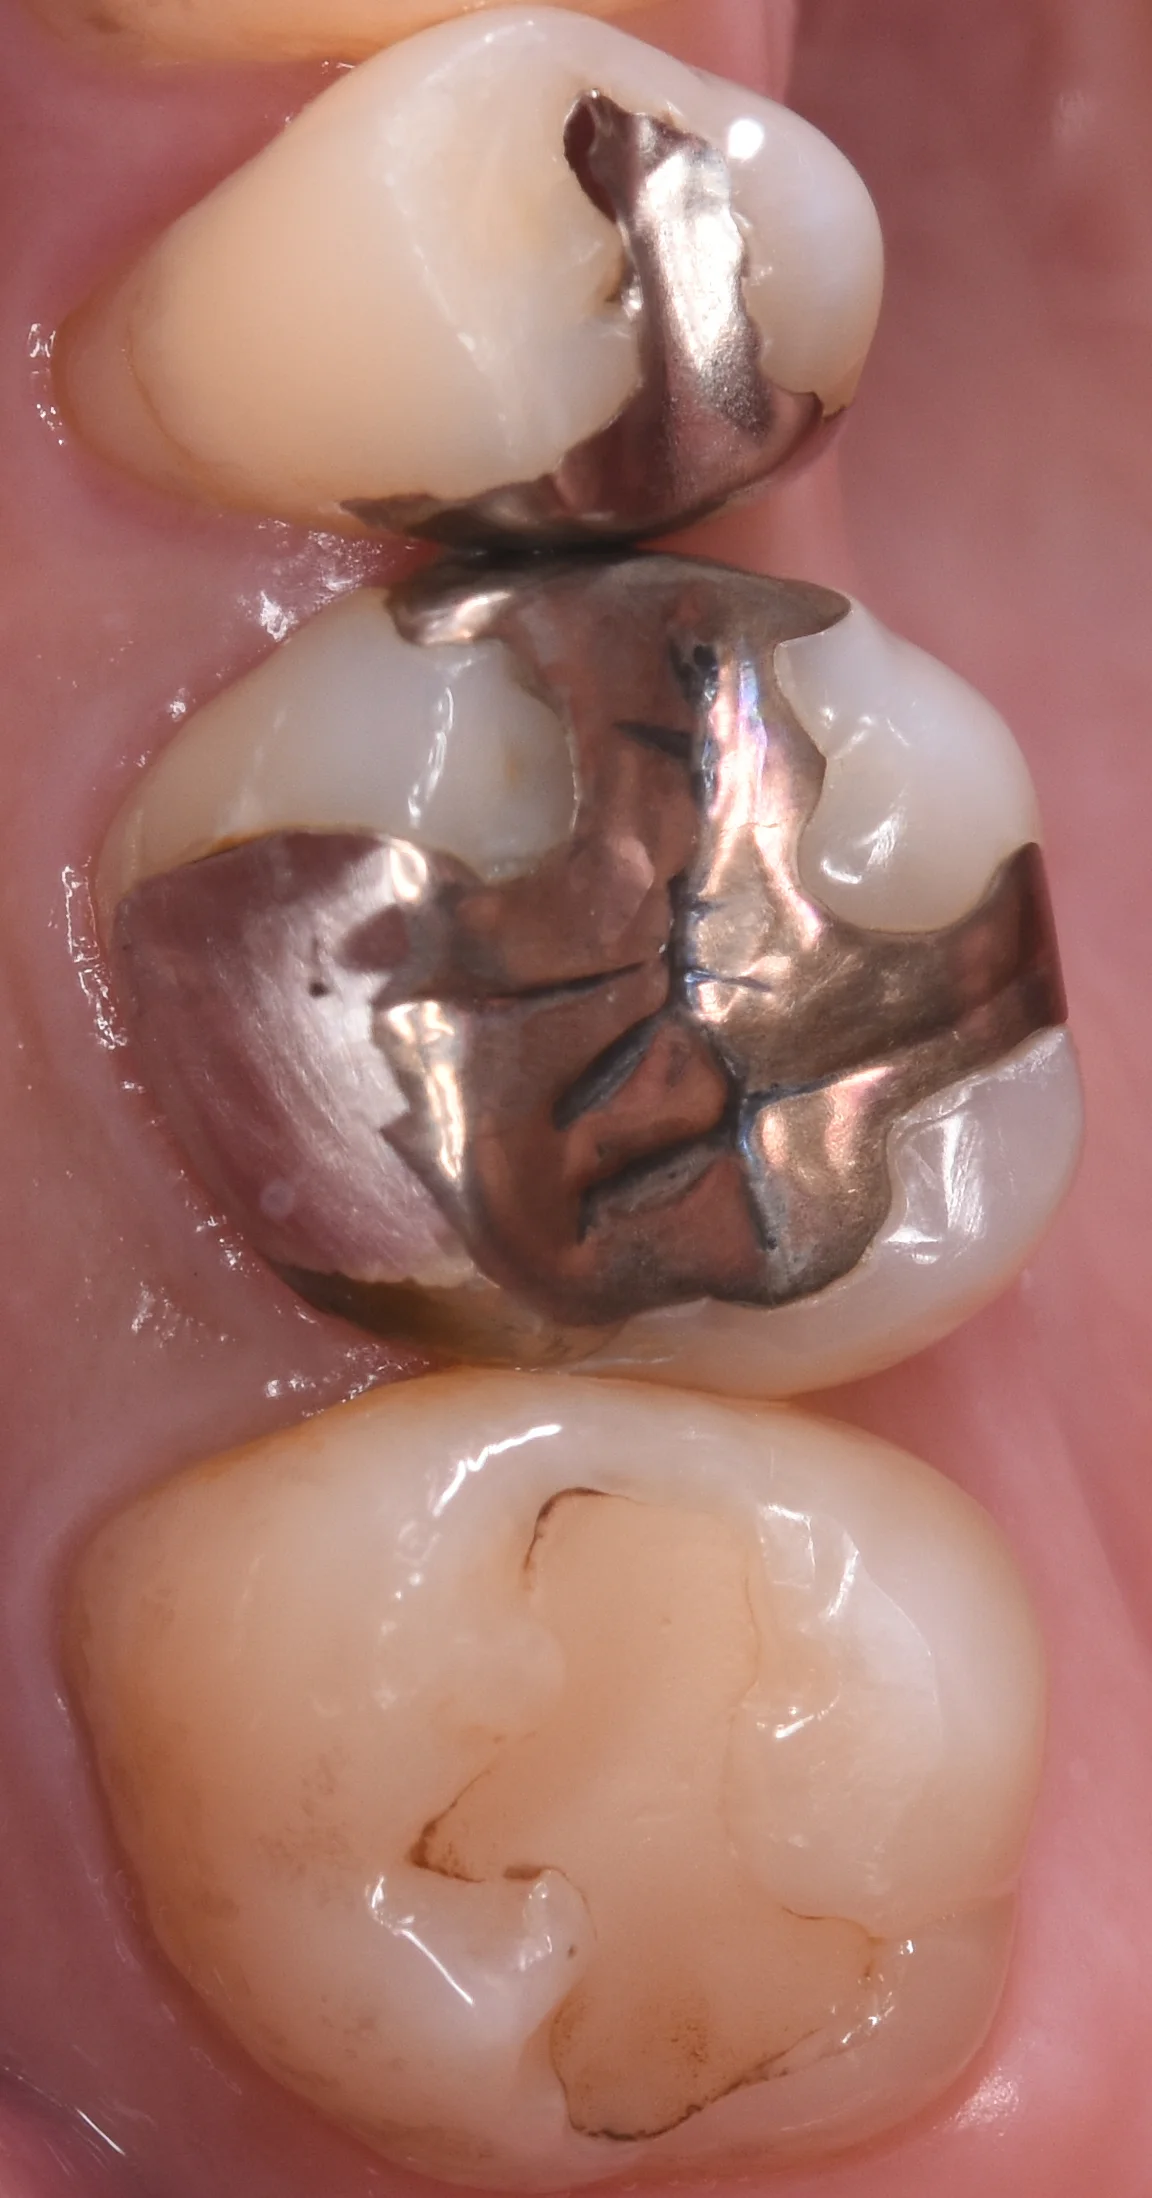

まずは術前からです。

金属を白い詰め物に。|坂寄歯科医院(取手市藤代)

3つの歯の真ん中にある金属の詰め物が入っている歯の治療を行なっていきます。

今回は頬側の方まで治療しているので一枚で治療箇所をわかりやすくするため、やや斜めから撮影を行なっています。

非常にわかりづらいですが、歯の根本の方に金属と白い詰め物がくっついているところがあります。

金属と白い詰め物の接着は非常に弱いので、こういうところから中に虫歯が入り込むことがよくあります。

おそらく前の先生は歯の根本の削れた部分を金属で隠そうとしたのかもしれませんが、それだと歯を削る量が多すぎるという判断でこのように半分だけ金属で覆ったのかもしれませんね。

もしくは金属の詰め物を入れた後で歯が削れたため、そこを埋めたのかもしれません。

まぁ実際にその場にいなかったので、想像に過ぎないですが(⌒-⌒; )

どちらにしてもこういった感じで異種材料を付けると長期予後に不利になることが多いため、私は基本的には除去し切るようにしています。